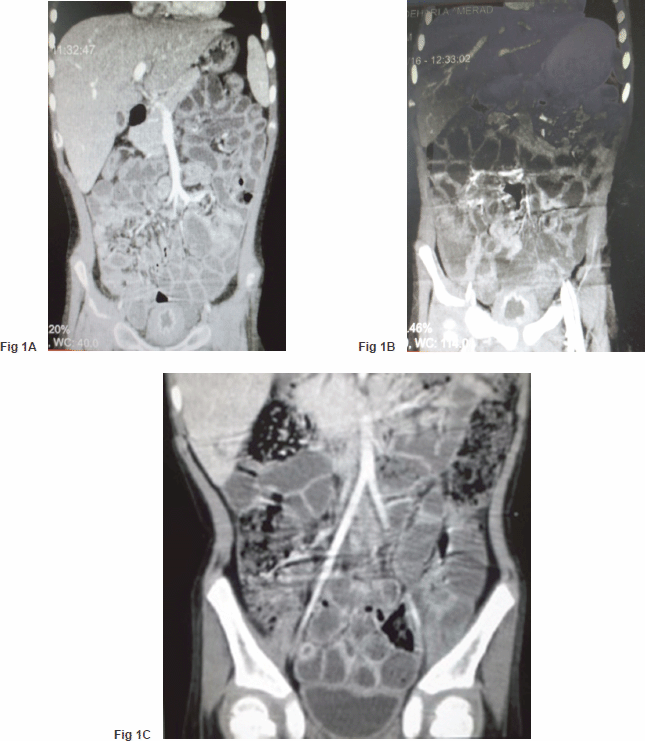

A five-year-old boy, a case of standard-risk ALL with t(12,21), developed a prolonged course of intermittent fever and productive cough at the end of the second year of maintenance chemotherapy. He was receiving chemotherapy protocol as ALL-BFM-90 with some modifications. Induction therapy consisted of vincristine, prednisone, doxorubicin, L-asparaginase (L-ASP) [(10,000 IU/m2), twice a week], and intrathecal chemotherapy, followed by consolidation therapy including cytarabine, L-Asp, etoposide, and intermediate dose methotrexate (1 g/m2) with leucovorin. Reinduction therapy was similar to induction therapy except that daunorubicin was substituted for doxorubicin and dexamethasone for prednisone, respectively. Cranial radiotherapy was not given to the patient. Continuation therapy consisted of 6-mercaptopurine and methotrexate along with vincristine and prednisone every three weeks. A thorough investigation was conducted for evaluation of the fever and cough. A bone marrow examination was compatible with remission; a chest computed tomography (CT) scan demonstrated diffuse patchy alveolar infiltrations. Investigation for fungal infections, including imaging studies and serum galactomannan assay, was negative, whereas cytomegalovirus pp65 assay on the sputum was indicated to be positive. Hence, he was determined to receive a course of ganciclovir along with the broad spectrum antibiotics including ceftazidime and vancomycin. The fever and cough improved significantly, and he was discharged after three weeks of treatment. Two days later, he came back with a severe dysuria and macroscopic haematuria. Aggressive hydration to ensure a urine output of 4–5 litres/day with 1/3 normal saline was started for the patient. His platelet counts and coagulation profile were normal. An imaging study of the urinary system, including a contrast enhanced abdominopelvic CT scan, showed a very thick walled bladder with distinct layering, perivesicular stranding, and intravesical clots [Figure 1(A)]. There was no recent history of treatment with cyclophosphamide in the patient. Accordingly, a urine sample was checked for BKV by real-time polymerase chain reaction (PCR), which was positive with increased loads to 1 × 105 copies/ml. At the same time, urine was also checked by PCR for cytomegalovirus (CMV) and adenovirus, which were negative. In addition, complementary for diagnosis, urine was examined for observation of decoy cells that were positive on centrifuged spot urine sample of the patient (Figure 2). The patient’s plasma was also tested and showed positive viraemia with BKV with 3,000 copies/ml of plasma. The patient was so frustrated that urinary catheterisation was inserted for the child through which bladder irrigation was performed. He also received intravenous immunoglobulin (IVIG), intravenous ciprofloxacin, and a combination of urinary antispasmodics; oxybutynin and phenazopyridine as local urinary analgesic to help in providing immediate symptomatic relief. The symptoms started to subside slowly so that during 10–12 weeks of conventional therapy, a decrease in bladder wall thickness was observed on repeated CT scans [Figure 1(B) and (C)]. Likewise, urine BK viral load started to decline; however, as mild degrees of dysuria was persistent for almost two months, the child discharged with oral ciprofloxacin and topical application of lidocaine and a mild steroid cream for symptomatic relief.

Figure 1. (A) Severe bladder wall thickness with distinct layering, perivesicular stranding, and reduced intravesical volume. (B) and (C) Remarkable improvement in bladder wall thickness and bladder space.